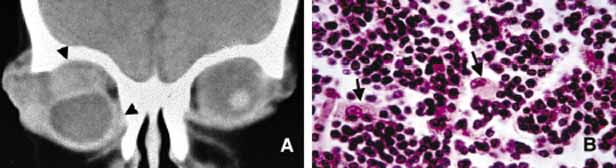

Tumor cells of schwannoma stain positive for S-100 protein but the positive immunoreactivity is not specific to this tumor; neurofibroma also demonstrates positive but weaker staining with S-100. On occasion, it may be difficult to distinguish a malignant peripheral nerve sheath tumor from other poorly differentiated sarcomas; in these situations, S-100 and GFAP positivity supports the diagnosis of peripheral nerve sheath origin.

Neurofibroma accounts for approximately 2% of all orbital tumors.222 This tumor, which is composed of neoplastic proliferation of Schwann cells, axons, and endoneural fibroblasts, may present as an isolated, diffuse or plexiform lesion. All cases of plexiform tumors and some of the diffuse ones are associated with neurofibromatosis and their other characteristics are also similar.229 The localized type is very rarely associated with neurofibromatosis. The plexiform neurofibroma usually presents at a young age as an eyelid lesion, which has been described with a consistency of “bag of worms.” Histopathologically plexiform neurofibromas consist of intertwined bundles of hypertrophic axons, endoneural fibroblasts, and Schwann cells that are compacted into well-demarcated cylindrical cores (Fig. 20). Diffuse neurofibroma is similar to its plexiform counterpart but the distinct bundle formation is absent. The solitary neurofibroma is also composed of groups of axons, Schwann cells and fibroblasts but it is well circumscribed. All three types stain positive with S-100 protein; however, the reactivity is less intense than schwannoma.230 In patients with neurofibromatosis malignant transformation of neurofibroma into neurofibrosarcoma develops in approximately 20% of cases.231

Choice of treatment for neurofibroma is surgical excision that is easily performed in circumscribed, solitary neurofibromas. This often proves to be very difficult for diffuse and plexiform lesions. Large lesions eventually are treated with exenteration.